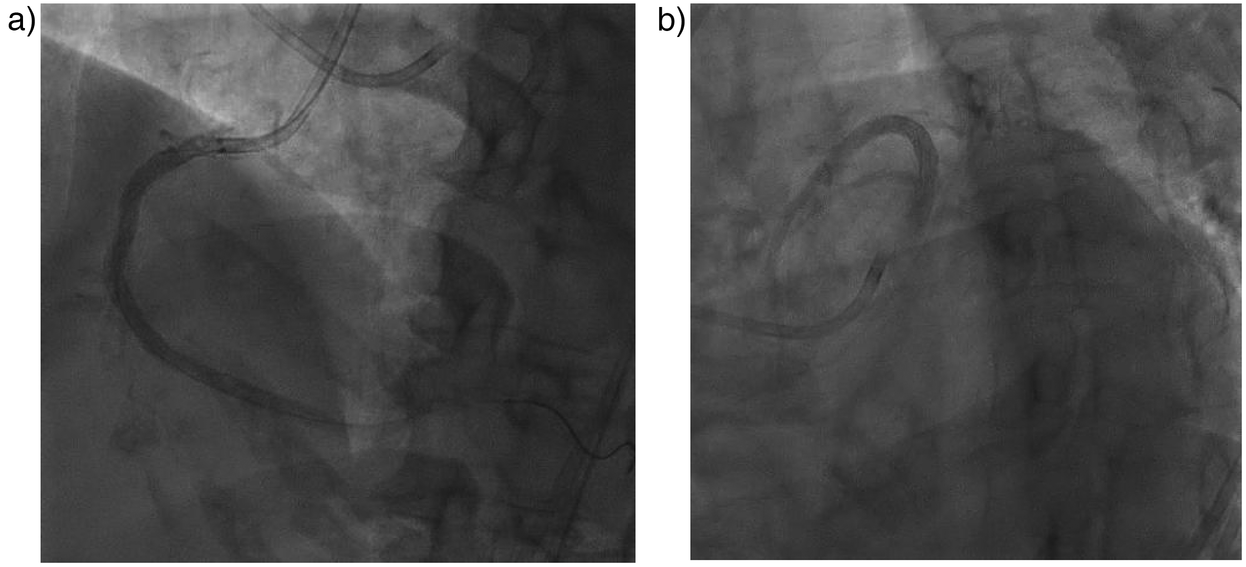

An anatomical marking technique was employed for the placement of both the distal and proximal landing zones. For the distal landing zone we utilized vertebrae as landmarks, while the proximal landing zone was guided by positioning an additional wire in the conus, allowing precise identification of the ostial location. A drug-eluting stent (DES) Promus Premiere 3.5 × 38 mm was implanted from the ostium to the mid segment, followed by the implantation of a mid to distal DES Xience Xpedition 3.0 × 38 mm. Balloon measurement was performed to ascertain the length of the DES in the mid region by evaluating the gap between the previously placed stents. Subsequently, a third DES Promus Premiere 3.5 × 16 mm was implanted in the mid-right coronary artery (RCA) (see Figure 1E). Angiographic evaluation was conducted using a hand injection of 0.5 cc of contrast (Figure 2), with the total contrast volume utilized during the procedure being only 5 cc. At one-year follow-up, our patient demonstrated a significant improvement in left ventricular ejection fraction (LVEF), increasing from 33% to 56%. Additionally, her symptoms resolved, with no reported chest pain. This patient showed no AKI. There was no significant decline in renal function, as the serum creatinine increased only slightly from 1.59 to 1.61 mg/dl and the estimated glomerular filtration rate (eGFR) decreased minimally from 39 to 38 ml/min/1.73 m2 over 72 h.

Figure 2

Post PCI angiography evaluation. (a) RCA stent and (b) LAD stent were in good position.